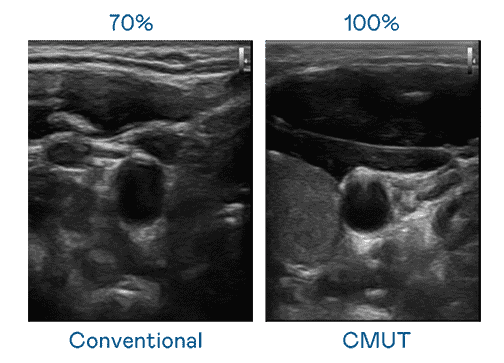

CMUT 技术是一种用电容式微机电元件来产生超音波讯号的技术。。。。与传统 PZT 压电式技术相比,,CMUT 频宽增加 30%,,,,更宽频的超音波讯号让影像解析度大幅提升,,,是实现高影像品质医疗超音波扫描、、、促进精准医疗发展的关键技术。。

大频宽带来超清晰影像

超音波影像的解析度高低,,首先取决于探头能发出的讯号频宽。。。EBpay CMUT 可提供高清晰的超音波讯号,,提供高频宽、、、、高灵敏度、、影像纹理细节更高的超音波影像,,,协助医护人员缩短影像判读时间及利用精准的医疗影像进行诊断。。。